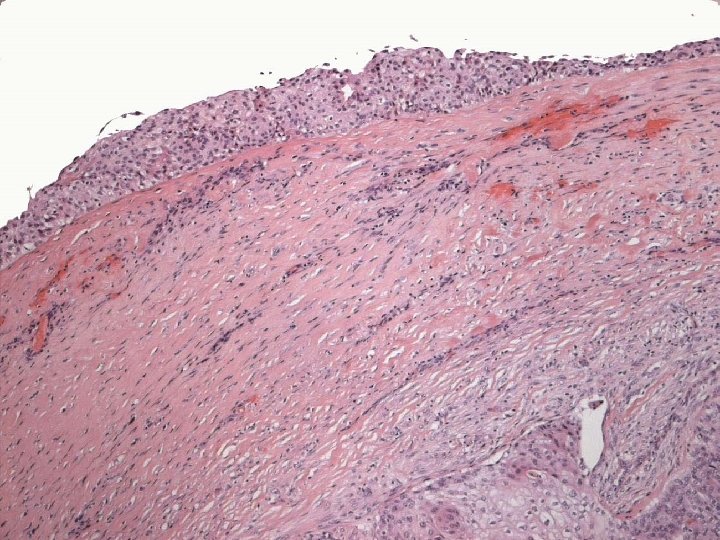

Micro n Similar to SCC at other sites n Cytoplasmic clearing in some

Micro The strongest evidence of a primary SCC of breast is presence of in-situ squamous carcinoma in duct or cyst lining.

Primary Squamous cell carcinoma A breast carcinoma entirely composed of metaplastic squamous cells that may be keratinising, non-keratinising or spindled; Exclude extension from skin and metastases. (WHO. 2003) Characterised by origin from squamous metaplasia in cyst, duct or both.